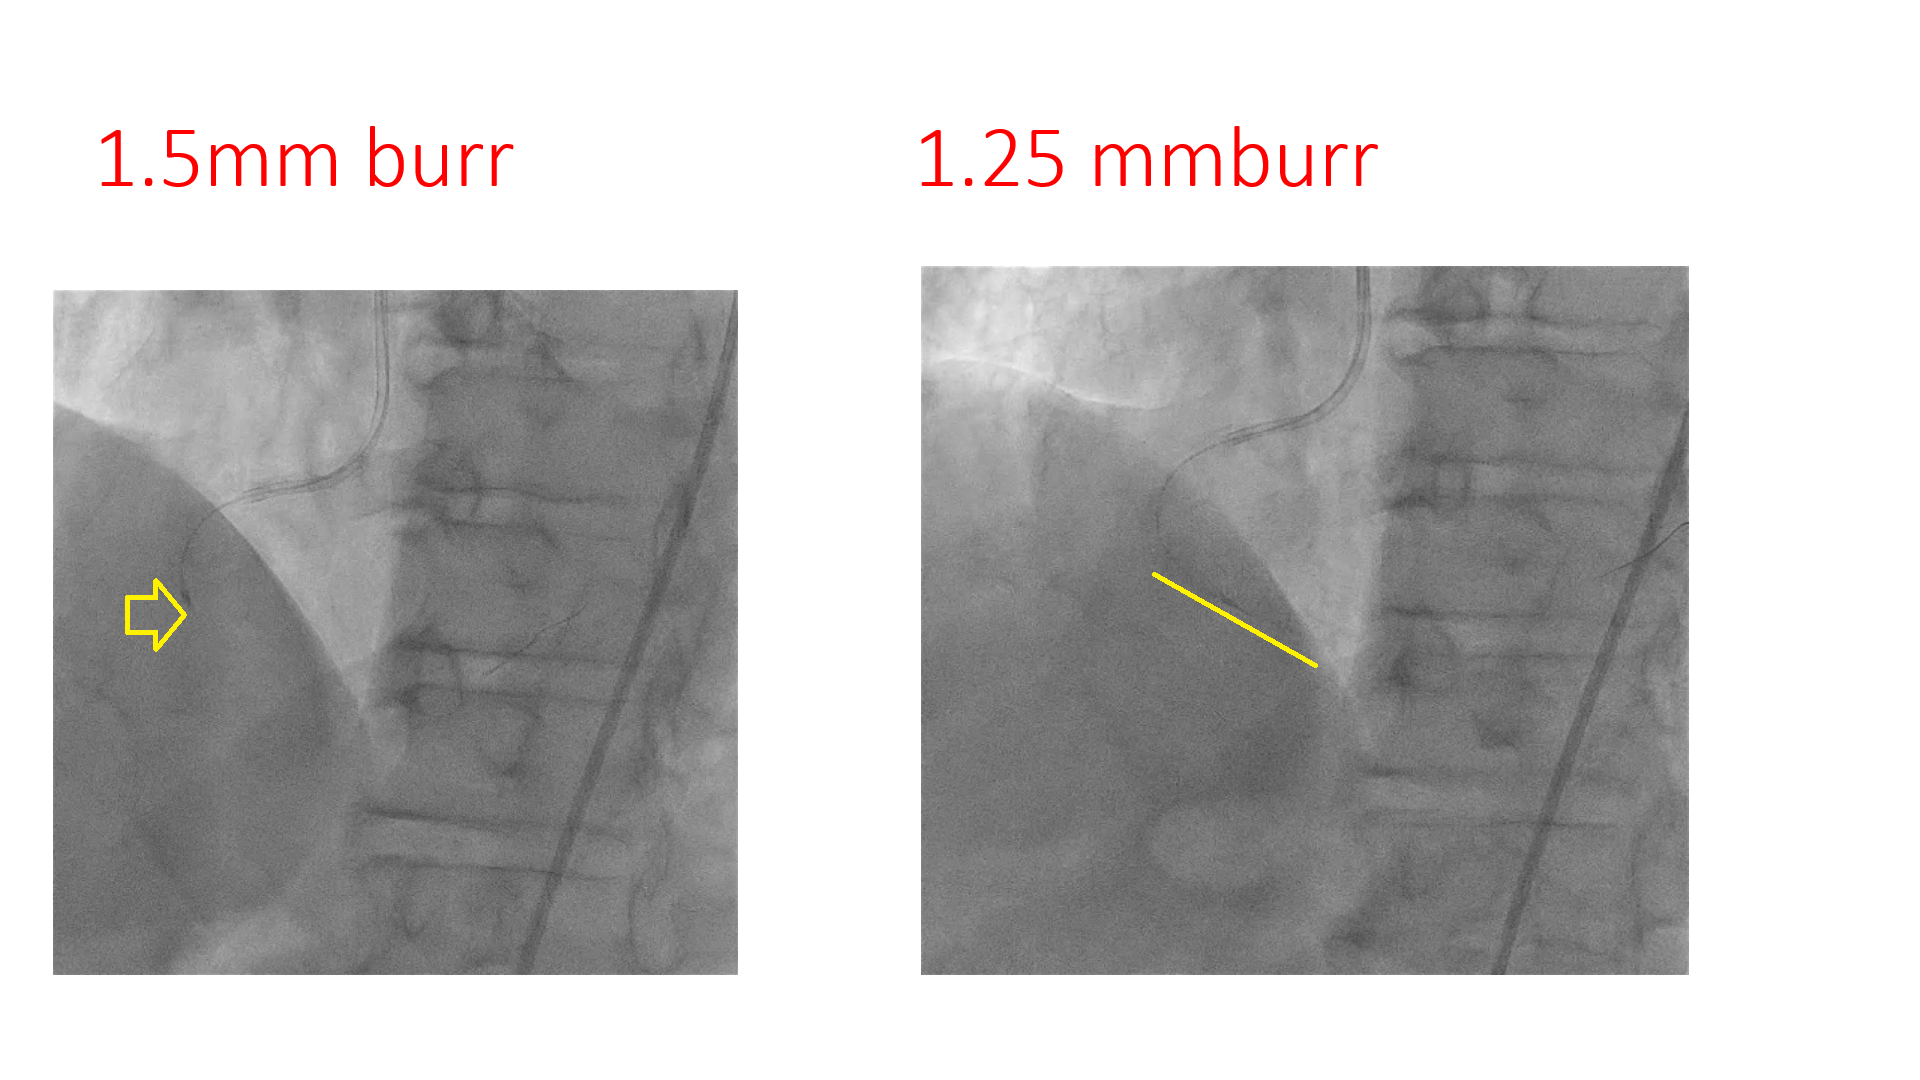

7F Femoralapproach and AL 0.75 was taken. Lesion crossed with Runthrough wire with fine cross support. Predicated with 1.5*5mm semicomplaint balloon , could not crossed and busted distally. ROTA 1.5mmburr, couldn't crossed at mid RCA, even at 200000 rpm speed, likely wire bias. ROTA 1.25mm burr crossed at 150000 rpm and after that, lesion was predilated with 2.5*15 mm semicomplaint balloon, and 2.75*15 mm non complaint balloon. Stent 2.5*38mm was deployed in distal-mid RCA at 12 atm, and proximal stent 3*32 mm was deployed in mid-proximal RCA at nominal pressure with Guidezilla support.Post stent dilation was done distally with 3*15 mm and proximally with 3.5x15mm Non-complaint balloon @ 16-18 atm. Good end result.

Step-down Rota burr strategy should be done early, in case of difficulty with regular burr. Wire bias does exist during Rota ablation. Tortuosity in vessel predisposes to wire bias in rotablation. Changing the wire to extra support or reducing the burr size: what should be done ideally and always matter of discussion.